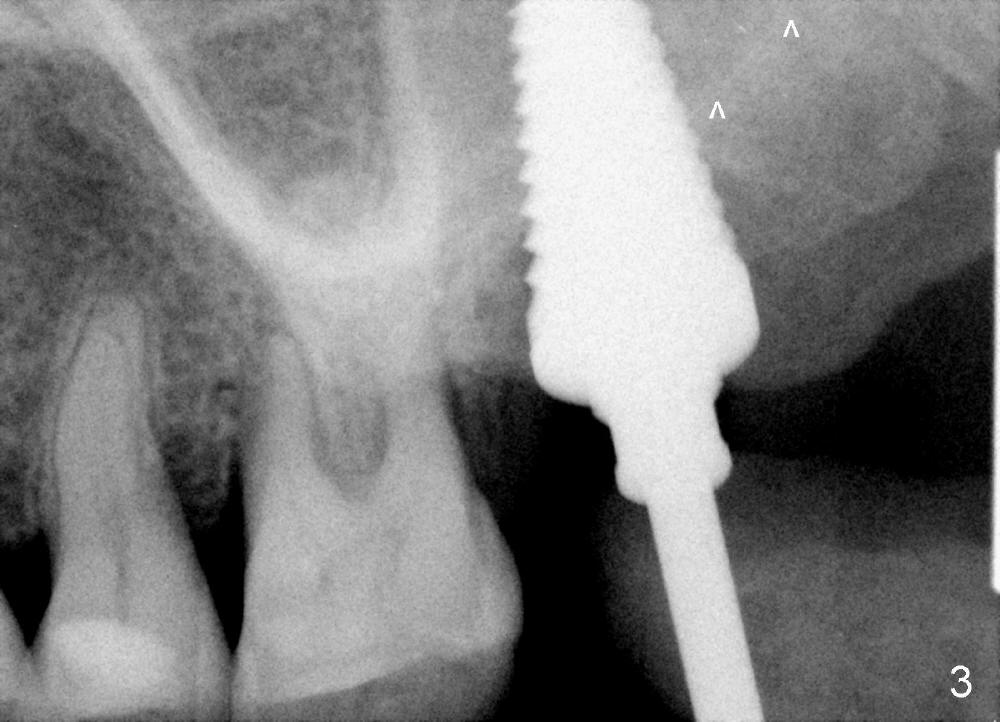

A 56-year-old female has recurrent infection and buccal gingival recession (Fig.1 *) after root canal therapy in the upper left 2nd molar (Fig.2). The extraction socket is single and large. Osteotomy forms by using a series of osteotomes (2-5 mm in diameter) mesiopalatal to the center of the socket. The sinus floor is thin (approximately 2-3 mm). The osteotomy is further enlarged by inserting 4.5-8 mm taps at the depth between 14 and 17 mm from the gingival margin. The last tap has barely achieved stability (Fig.3). It appears that the tap has almost obliterated the socket. Allograft is pushed into the sinus before placement of a 8x17 mm implant. The insertion torque is between 15 and 20 Ncm (Fig.4). The gingiva-level implant is slightly subgingival except buccal (Fig.5). To facilitate buccal gingival re-growth and cover the exposed implant surface, bone graft is placed subgingival (Fig.5 ^). The gingival sulcus is closed partially by placement of a thin strip of collagen membrane (not shown). The wound is protected by applying perio dressing.